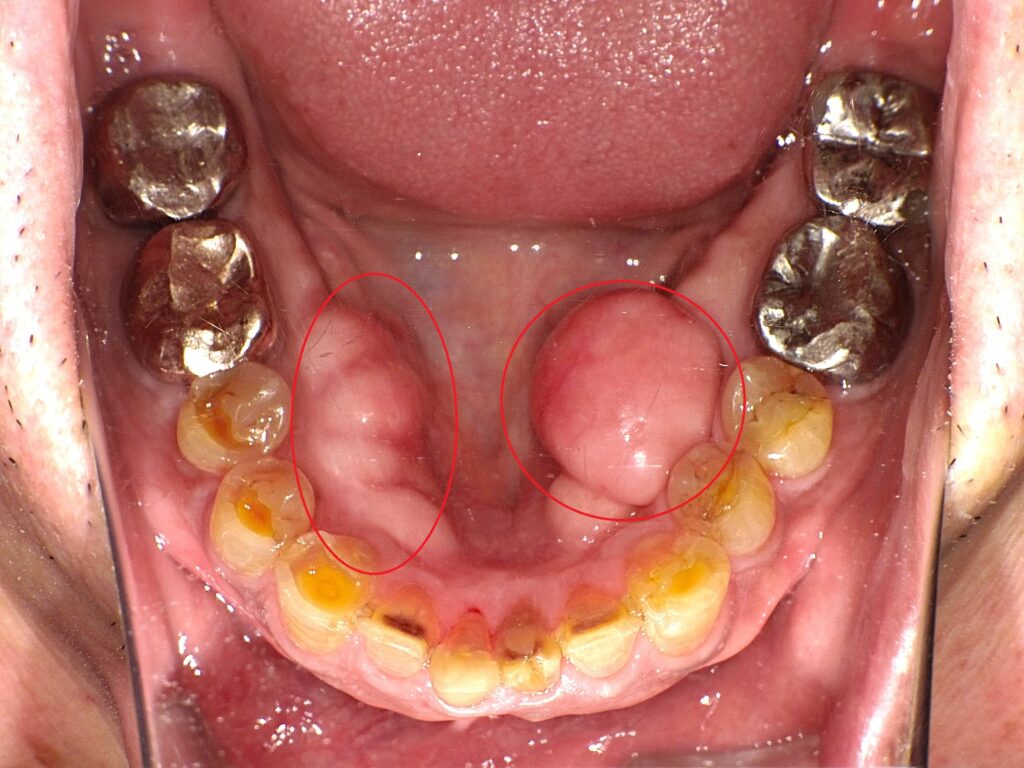

特に、下あごの内側に左右に大きなふくらみがある場合、

それは「骨隆起(こつりゅうき)」と呼ばれるものかもしれません。

骨隆起とは、あごの骨が部分的に盛り上がってできる骨の出っ張りです。

多くの場合、下あごの内側(舌側)に左右対称に見られます。

上の写真のような下あごの骨隆起を特に下顎隆起といいます。